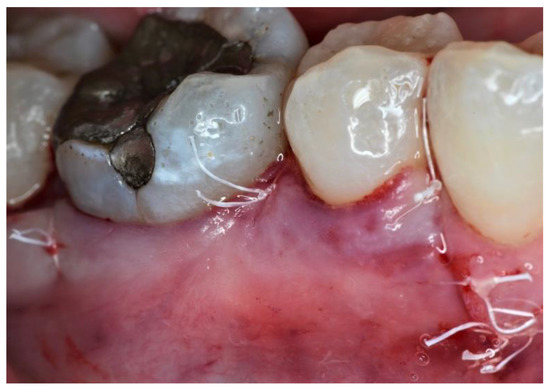

2. Case Series

2.2. Clinical Findings

2.3. Therapeutic Intervention